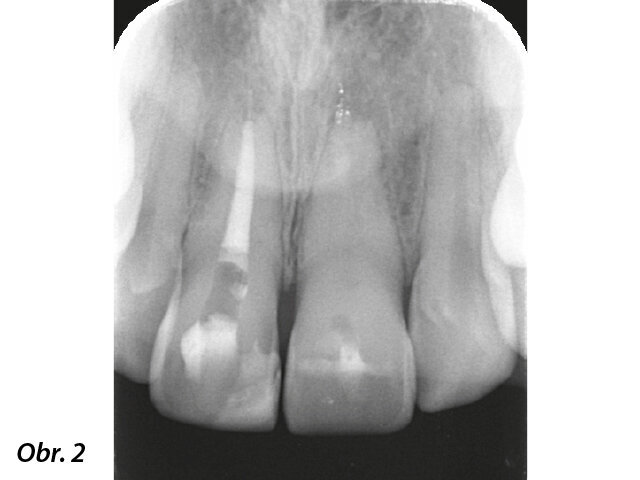

Pacientka, 22 let, byla do privátní kliniky odeslána s bolestí v horního levého středního řezáku v anamnéze. O 9 let dříve prodělala pacientka zubní trauma. Zub byl zbarven dožluta a reagoval citlivě na poklep (obr. 1). Testy vitality chladem a elekrotesterem byly negativní. Radiologické vyšetření ukázalo značně kalcifikovaný kořenový kanálek (obr. 2). Přítomnost radiolucence odpovídající apikální periodontitis byla potvrzena CBCT skenem (i-CAT, Imaging Sciences International) (obr. 3).